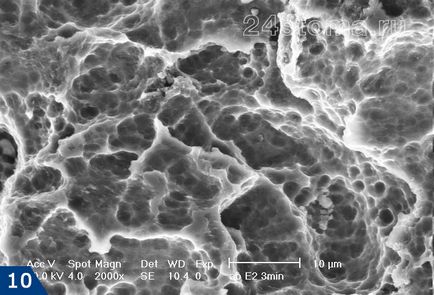

1) A mikroporózus felületi implantátumok «Nano Tec» (ábra10) -

Felületi «Nano Tec» jelentősen növeli a felület érintkezési az implantátum a csont felületén (például a felületével összehasonlítva a típusú RBM) terület, javítja a kezdeti stabilitását az implantátum a csontban közvetlenül behelyezés után. RBM felületek típusú kapjuk csak útján homokfúvással.